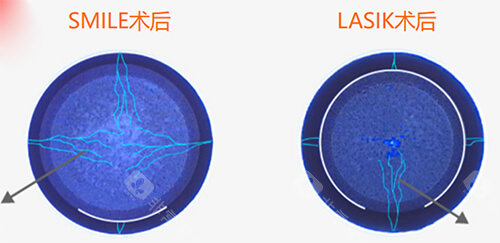

全飞秒激光手术:15800元/双眼